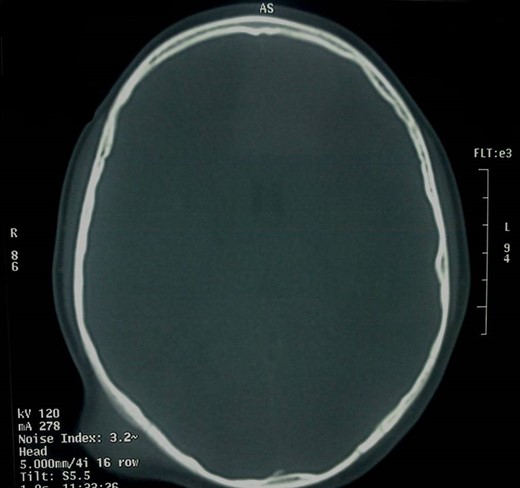

Α 12-year-old girl presented to us with a painless tumefaction on the right suboccipital region evolving for 5 months. Clinical examination did not reveal any other important symptoms or signs. Various explorations carried out, in particular, X-rays (Fig. 1), CT scan with intravenous contrast medium (Figs 2 and 3) and imagery by magnetic resonance with intravenous paramagnetic contrast.

Head profile X-ray. Bone thinning (white arrow) caused by the mass (red arrow).

The CT scan showed that there was only thinning of the bone without erosion or intracranial extension of the mass. There were no signs of calcification, and there was a mild and inhomogeneous uptake of the contrast.